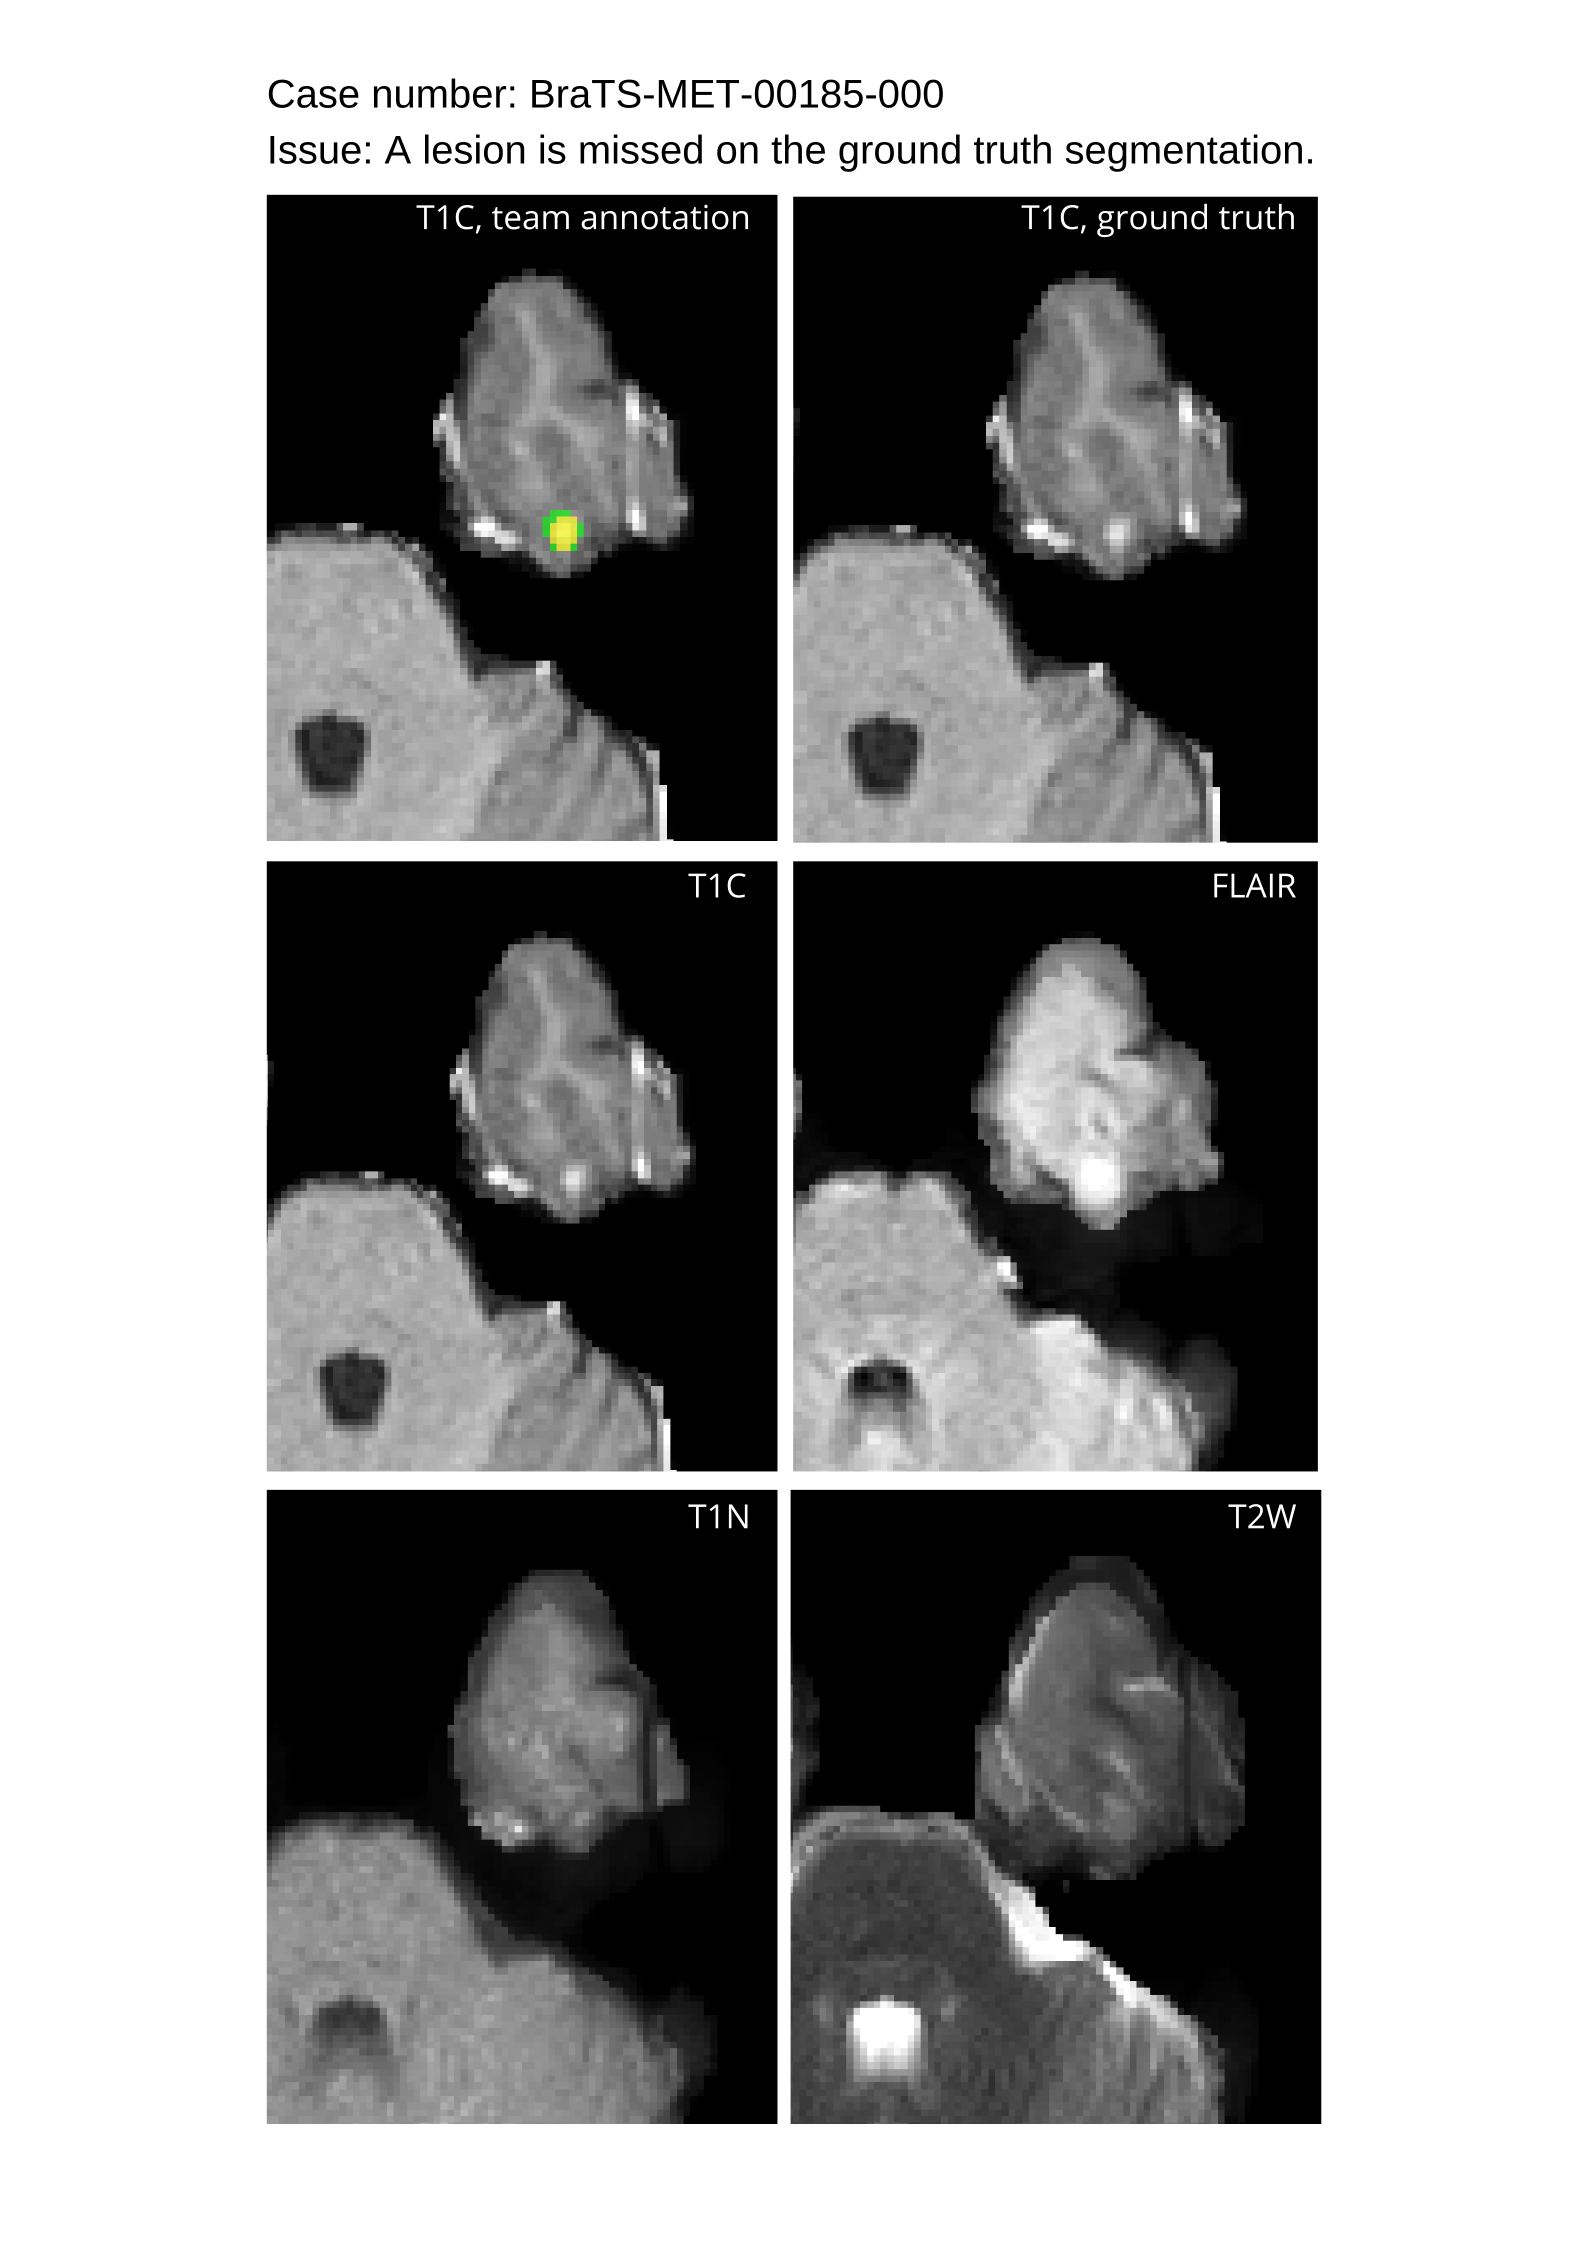

Table 4 provides the relative ranking for each team. Team NVAUTO ranked first in the challenge, with an average rank across subjects of 7.9 and a PatientWise mean of 0.38. Team SY placed second with a PatientWise mean of 0.41 across all patients. The supplementary material depicts the pitfall cases with figures illustrating the false positives or missed lesions.